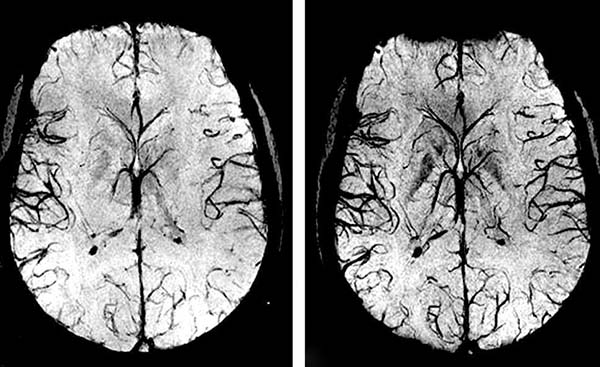

És minél több szennyeződés halmozódik fel az erekben, annál súlyosabbak lesznek a következmények. Az agyi erek közepes vagy súlyos szennyeződései esetén nagyobb valószínűséggel fordulhat elő stroke és teljes vagy részleges bénulás.